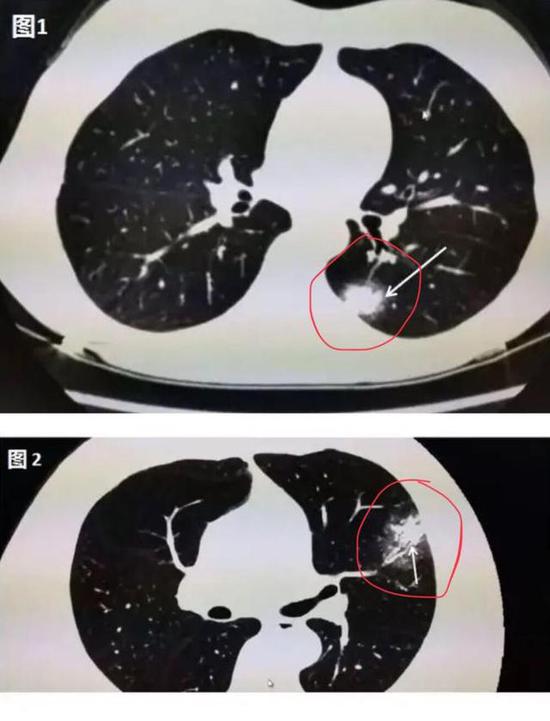

下图是新冠肺炎患者在做肺部CT时的图像,肉眼可见的红色圈内或白色箭头所指区域,相较于肺部其他正常部位出现了像云雾状磨砂玻璃一样的“病灶”,医学上美其名曰“磨玻璃影”。

▲新冠肺炎患者肺部CT显示磨玻璃影(图片来自网络)

其实,在疾病早期,肺部CT上可能并不会首先出现磨玻璃影。华中科技大学同济医学院附属同济医院放射科管汉雄教授发文称,患者一旦出现咳嗽、持续发热、不明原因乏力时,CT常常会有阳性发现。肺部CT上可能出现一白色不规则的小斑片(如图1箭头所指区域),即“实变结节影”,或者是中央实变、周围磨玻璃(如图2箭头所指区域),也就是中央区域是一白色不规则的小斑片,周围则像云雾状磨砂玻璃一样。随着病毒的持续“攻击”,病情发展,感染加重,白色的实变结节区域开始吸收,如同一颗糖融化了一样,慢慢变为磨玻璃影。

▲图1:肺部CT上出现一白色的小斑片; ▲图2:中央区域是一白色的小斑片,周围则像云雾状磨砂玻璃一样(图片来自网络)